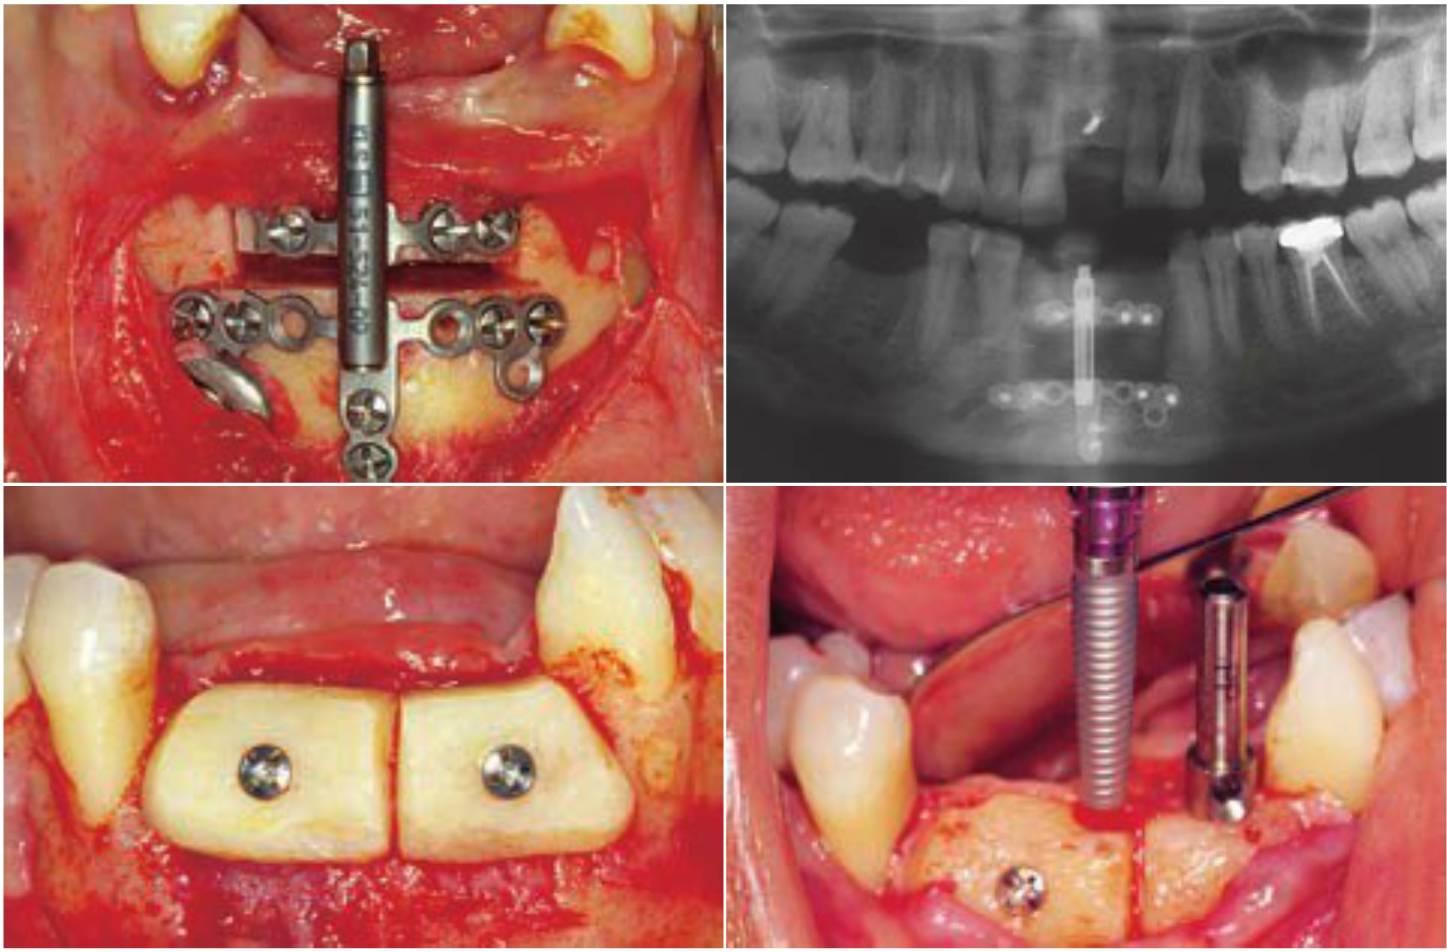

La osteogénesis por distracción presenta varias ventajas para el crecimiento vertical del hueso, respecto de las técnicas de injerto óseo onlay. La ganancia de hueso vertical no se ve limitada por factores como el tamaño del injerto o la expansión del volumen del tejido blando existente. No existe morbilidad del área donante y se puede realizar la cirugía en el gabinete dental. Sin embargo, la distracción ósea requiere de la colaboración del paciente y el aumento de volumen óseo es unidireccional. Además, los estudios clínicos han encontrado que, a menudo, se necesitan posteriores procedimientos de aumento de hueso para la colocación de los implantes dentales70. Misch presentó una técnica única en la que combinaba la distracción ósea vertical con injertos de hueso onlay horizontales para la reconstrucción tridimensional del defecto. Primero se realiza la distracción ósea para aumentar la cresta verticalmente y expandir el volumen del tejido blando. Seguidamente, se usa un injerto óseo onlay para terminar de repara el defecto (fig. 6-29).